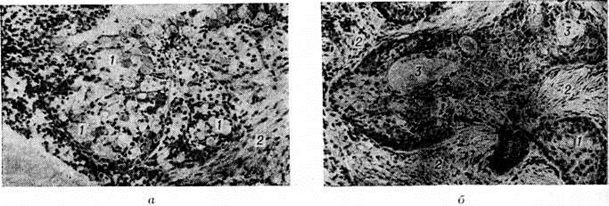

Рис. 3

Микропрепараты мукоэпидермоидных опухолей: а — скопления светлых слизеобразующих клеток (1) в строме (2); б — тяжи клеток плоского эпителия (1), прослойки стромы (2), кистозные полости (3) × 120